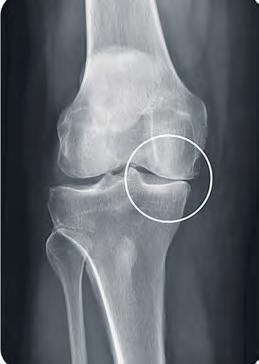

Schmerzen in den Griff bekommen

Wie Orthesen bei Arthrose das Leben erleichtern können

REGION – Wenn das Knie schmerzt, ist oftmals Arthrose das Problem. „Es gibt in Deutschland mehrere Millionen Menschen, die an der Erkrankung leiden. Die Betroffenen beobachten zum Beispiel Entzündungsschübe, Verdickungen und Verformungen an Knien, Fingern und an weiteren Gelenken“, erklärt Thorsten Belkot, Orthopädietechniker bei Oesterreich Orthopädietechnik. Betroffene könnten oftmals durch hochmoderne Orthesen, die die Gelenke entlasten und dadurch die Schmerzen reduzieren, zu einem aktiveren Alltag mit mehr Lebensqualität zurückkehren, so der Fachmann. Dabei sei es durch die gezielte Gelenkentlastung möglich, ganz normal wieder spazieren zu gehen oder auch moderat Sport zu betreiben. Oesterreich Orthopädie-Technik führt spezielle Orthesen für leichtere, aber auch für fortgeschrittene Kniearthrosen. Thorsten Belkot bietet Betroffenen die Möglichkeit, die innovativen neuen Entlastungs-Orthesen

Gelenkverschmälerung auf der Knie-Innenseite ohne Orthese.

der Firma Össur während der Arthrose-Testwochen auszuprobieren. „Die klinisch nachgewiesene Wirksamkeit sowie eine einfache Handhabung der Orthese sprechen für sich“, betont Belkot.

Als am stärksten belastetes Gelenk des menschlichen Körpers ist das Knie am häufigsten von arthrotischen Veränderungen betroffen.

Zugrichtung zur Entlastung des Gelenks auf der Knie-Innenseite.

Heilbar sind Arthrosen nicht. Es gibt jedoch effektive Methoden, um den Schmerz in den Griff zu bekommen und so eine eventuelle Operation weit hinauszuzögern.

Oesterreich Orthopädietechnik bietet vom 24. April bis 5. Mai spezielle Beratungen rund um das Thema Arthrose und kostenloses austesten einer Orthese an.

Gelenkerweiterung auf der Knie-Innenseite mit Orthese. Fotos: Oesterreich

Anmeldungen nimmt das Team unter Telefon 79 00 30 sehr gerne entgegen. Die beiden Orthesen-Testwochen finden in allen drei Bremer Filialen in der Bürgermeister-Smidt-Straße 32–36 (nähe Hauptbahnhof), Berliner Freiheit 1e (Vahr) und in Stader Straße 35 (Peterswerder) statt. Weitere Informationen unter www.ot-oesterreich.de. WR